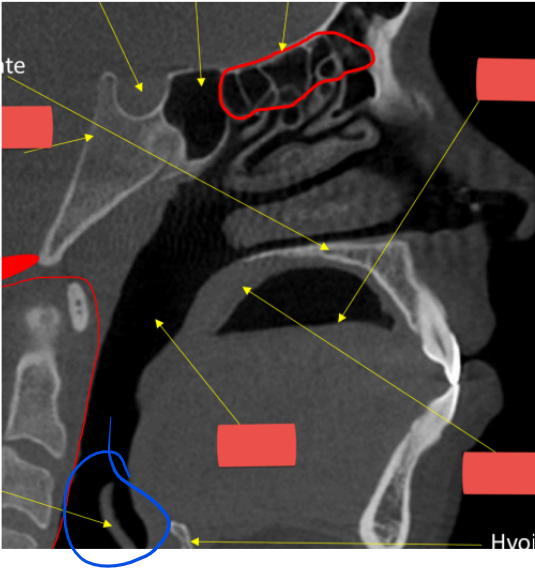

epiglottis

soft palate

hyoid

hard palate